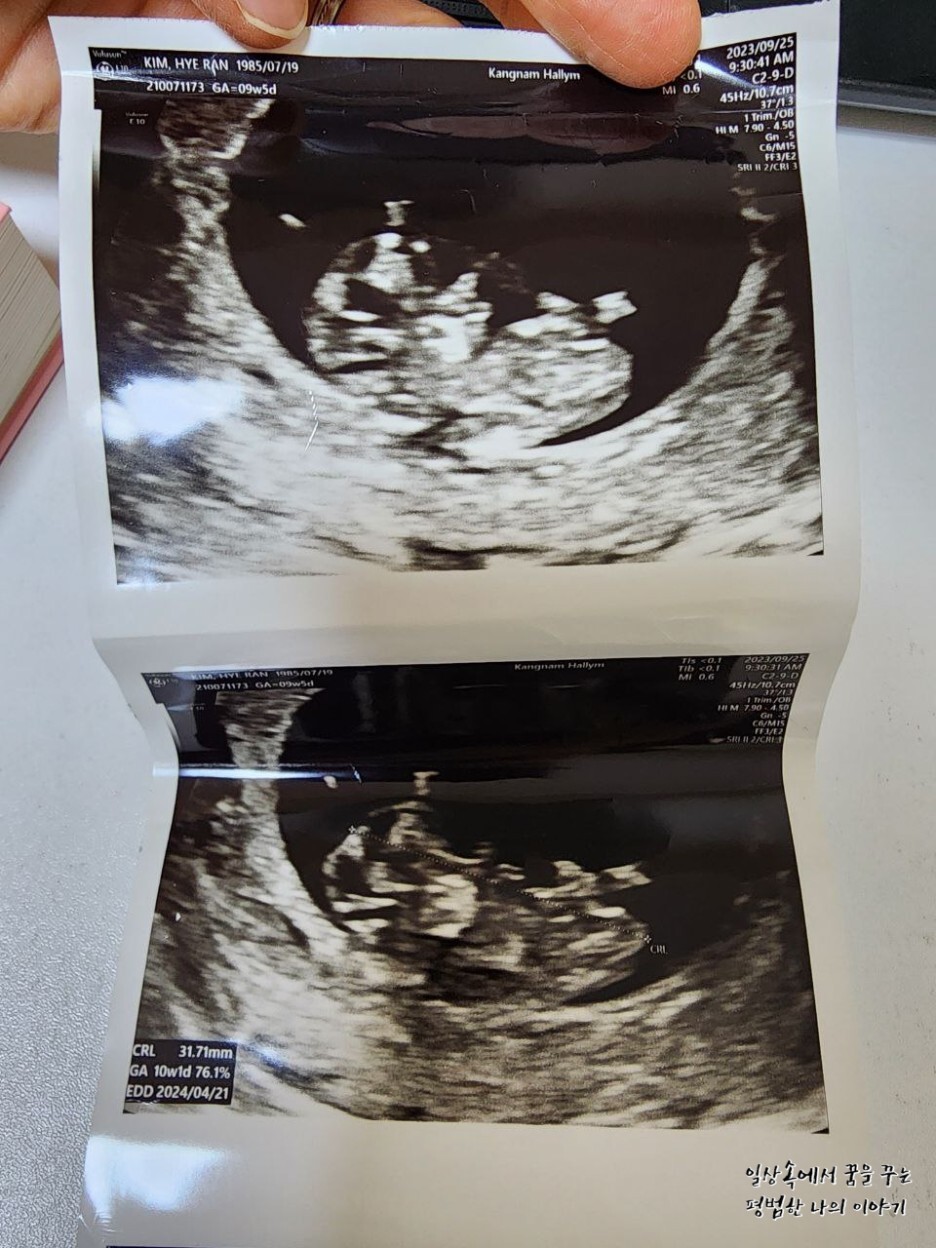

2023년 9월 25일(월요일)

EDD(Expected Date of Delivery, 출산 예정일): 2024년 4월 21일

FHR(Fetal Heart Rate, 심장박동 수): 176bpm

CRL(Crown-Rump Length, 태아의 머리부터 엉덩이까지의 길이): 31.71mm

소견: 무척 활발해서 한시도 가만히 있지 않음

2주 만에 만난 레오나는 여전히 내 눈에 귀여운 젤리 곰 형태를 하고 있었다. 2주 사이에 16.72mm에서 31.71mm로 두 배나 길어져 있었다. 31.71mm라고 해봐야 정말 콩알만 한 크기이지만 그 작은 크기에도 얼굴, 손 그리고 발까지 초음파로 확인이 가능하다. 출산 예정일은 지난번에 비해 3일 앞당겨졌는데 아기의 크기에 따라 계속 바뀔 수 있으므로 대략 4월 셋째 주쯤 출산하겠구나 예상하고 계획을 짜기 시작했다.